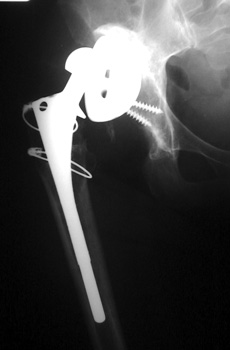

No prior studies available. Abnormally widened interfaces about femoral component at Gruen zones 1, 6, and 7. Osteolysis at Gruen zone 5 with marked thinning of femoral cortex placing patient at risk for pathologic fracture.